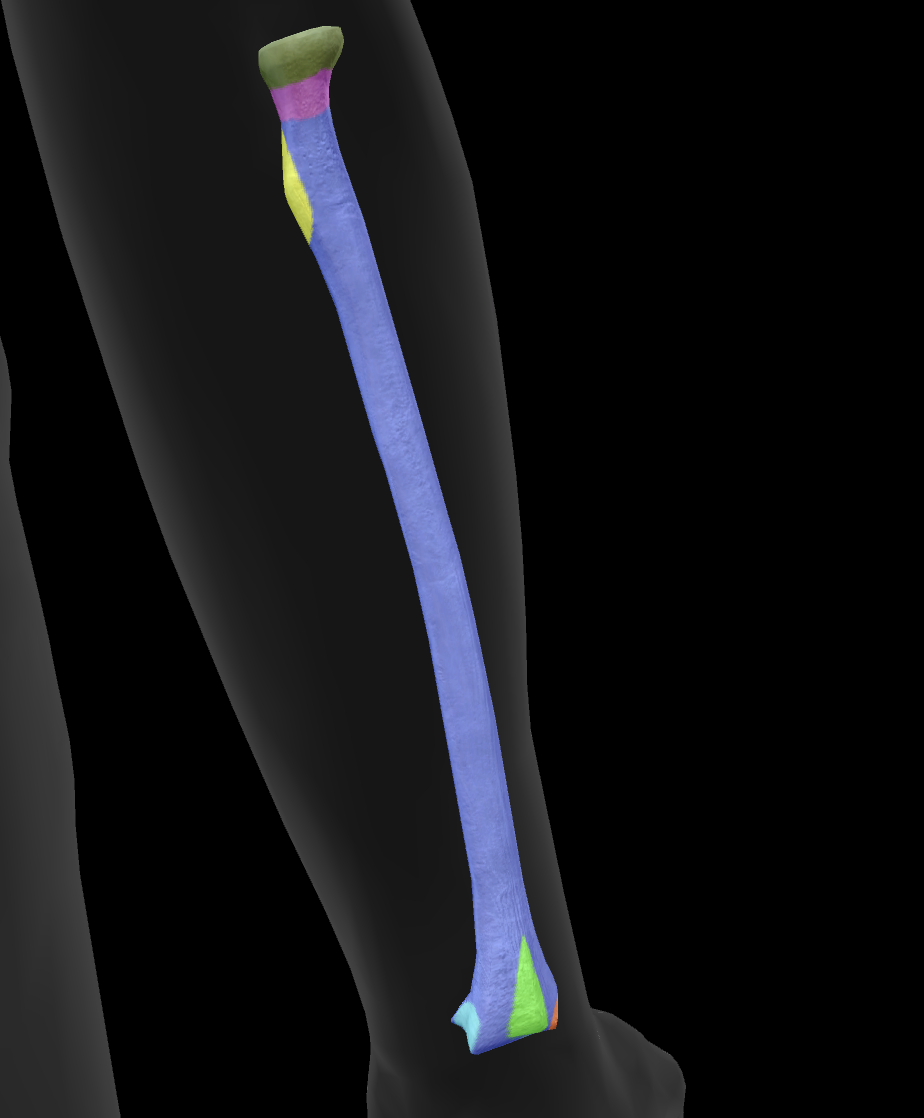

What is this bone?

radius

What is this boney landmark?

head

What is this boney landmark?

neck

What is this boney landmark?

radial tuberosity

What is this boney landmark?

shaft

What is this boney landmark?

radial styloid process

What is this boney landmark?

ulnar notch

What is this boney landmark?

lister’s tubercle